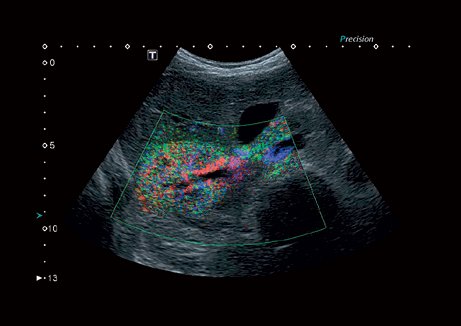

B, M, PWD, CWD, ЦДК, THI, 4D, динамический поток (Dynamic Flow), энергетический доплер (Power), контрастная эхография (CHI 2D) и комбинированные режимы, включая следующие: B/M, B/PWD, BDF/PDW, BDF/MDF,BDF/MDF/PWD, 2D/CWD, BDF/CWD (BDF-режим изображения, в котором CFM изображение накладывается на B-режим изображения, MDF-режим изображения, в котором CFM изображение накладывается на M-режим изображения)

• VRI - распознавание кровотока и тканевой перфузии

• Специальная фильтрационная технология выявления микрокальцинатов в молочной железе MicroPure;